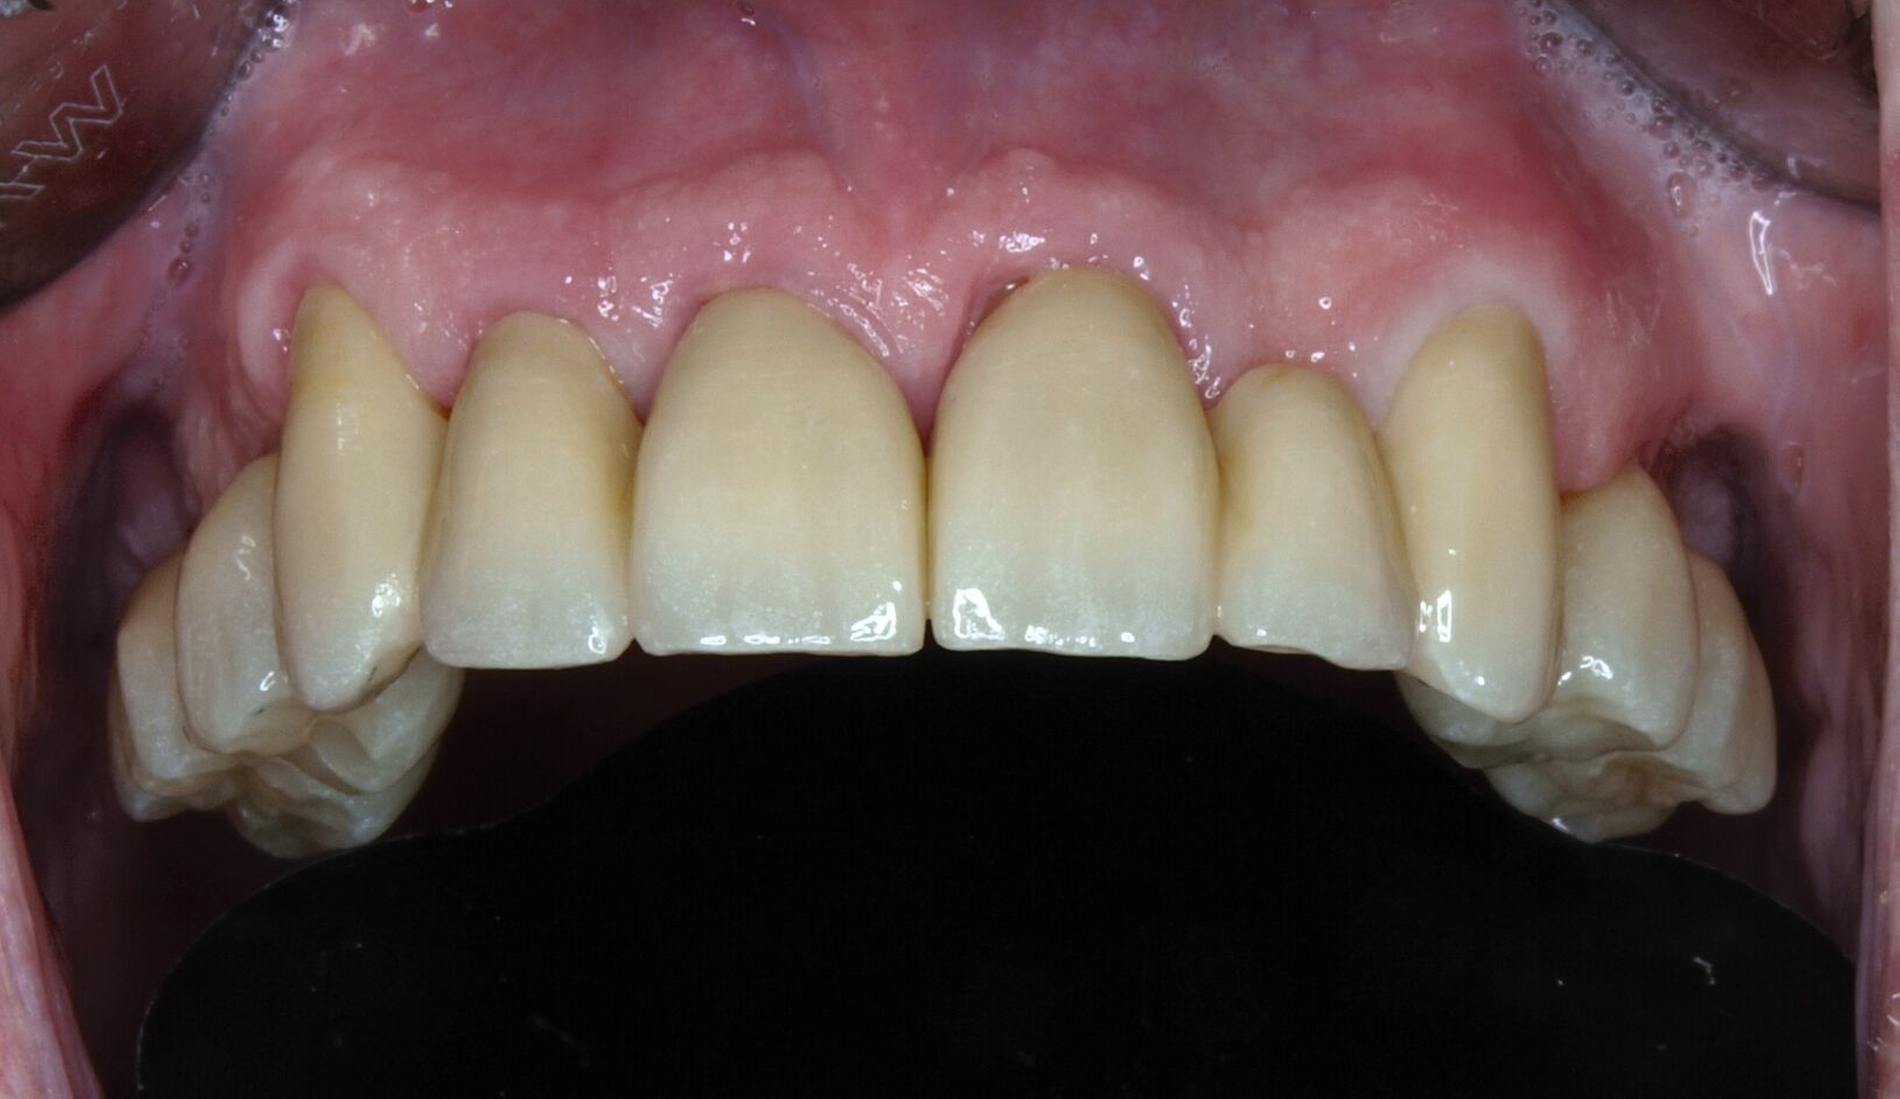

Nach Durchführung einer dentalen Volumentomografie (DVT) wurden daher zahnärztliche Implantate in Regio 14, 15 und 25 im Sinne einer verkürzten Zahnreihe geplant und inseriert (Abbildung 7). Nach dreimonatiger subgingivaler, konventioneller Einheilzeit wurden die Implantate freigelegt. Zwei Wochen später begann man die vorhandenen Primärkronen zu entfernen. Die Stümpfe wurden nachpräpariert und es wurden erneut Fäden gelegt (Abbildung 8a und 8b).

Nachdem die Einheilkäppchen entfernt und die Scanbodies in die Implantate eingeschraubt wurden, erfolgte der Intraoralscan (Abbildung 8c). Der festsitzende Zahnersatz wurde im zahntechnischen Labor designt und aus monolithischem Zirkonoxid gefräst. Die Kronen konnten schließlich selbstadhäsiv auf den Stümpfen befestigt werden. Das Einschrauben der Implantatkronen erfolgte mit Drehmomentschlüssel auf 35 Ncm nach Herstellerangabe. Die Schraubkanäle wurden anschließend verschlossen. Mit dem Endergebnis (Abbildung 8d) zeigte sich der Patient auch im Recallverlauf hochzufrieden.